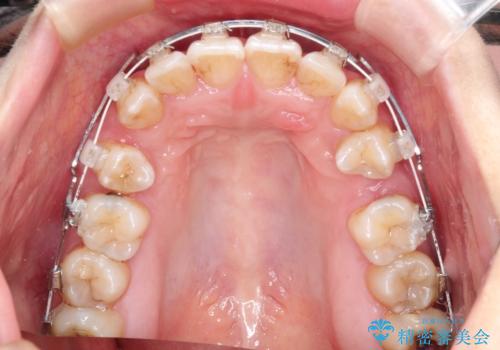

- 審美装置(ブラケット:白/ワイヤー:白)

抜歯ありワイヤー矯正にて治療を行い、抜歯する歯に関しては虫歯で抜歯が必要な部分を有効活用することで、健康な歯を保存するように努めました。

噛み合わせが深い過蓋咬合という状態でもあったため、下の歯の装置をつけたり、嚙み合わせを上げる(下の歯が見える状態にする)ことにたいへんに苦労した症例でした。